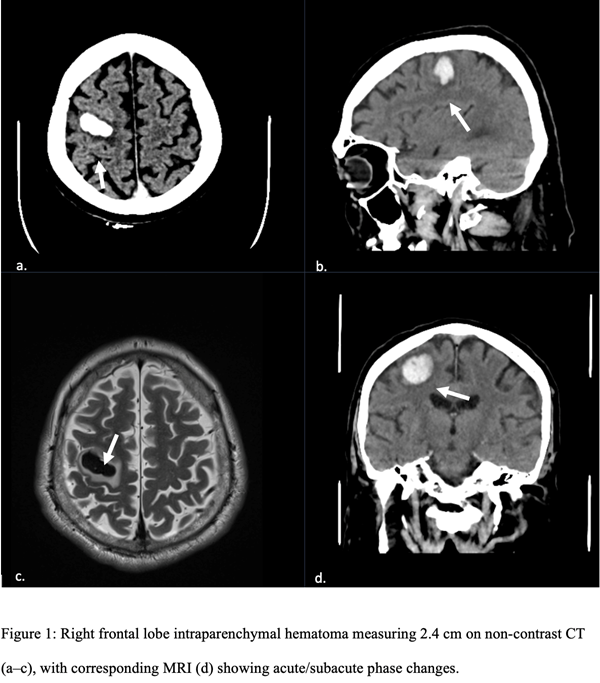

Chest X-ray and upper extremity Doppler studies were unremarkable. A non-contrast head computed tomography (CT) revealed a right frontal intraparenchymal hemorrhage measuring 2.5 × 1.2 cm with mild edema but no midline shift (Figure 1). Magnetic resonance imaging (MRI) confirmed the lesion in the hand knob region and excluded vascular malformations.